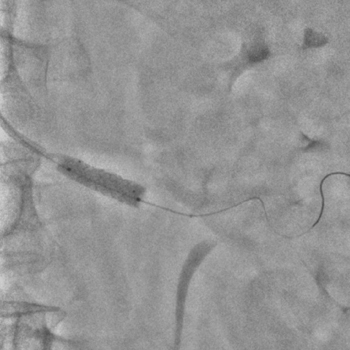

Бифуркационное стентирование почечной артерии

Ангиографическое исследование аорты и селективная ангиография сосудов почек выявило критический стеноз a. segmenti inferioris и короткую a. renalis sinistra

Операторы: Андрей Мальцев, Дмитрий Лебедев